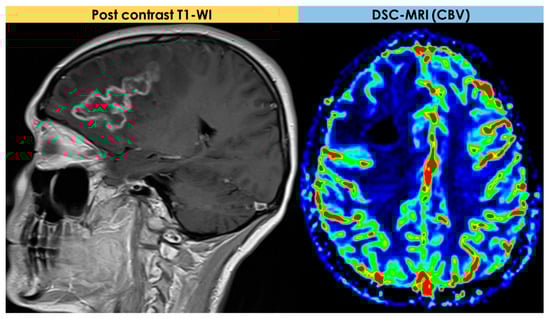

2.4. Advanced MRI Findings

- Dynamic susceptibility contrast (DSC) imaging, which is currently the most commonly used technique;

- Dynamic contrast-enhanced (DCE) imaging (both requiring intravenous administration of a gadolinium-based contrast medium);

- Arterial spin labeling (ASL), not requiring contrast media.